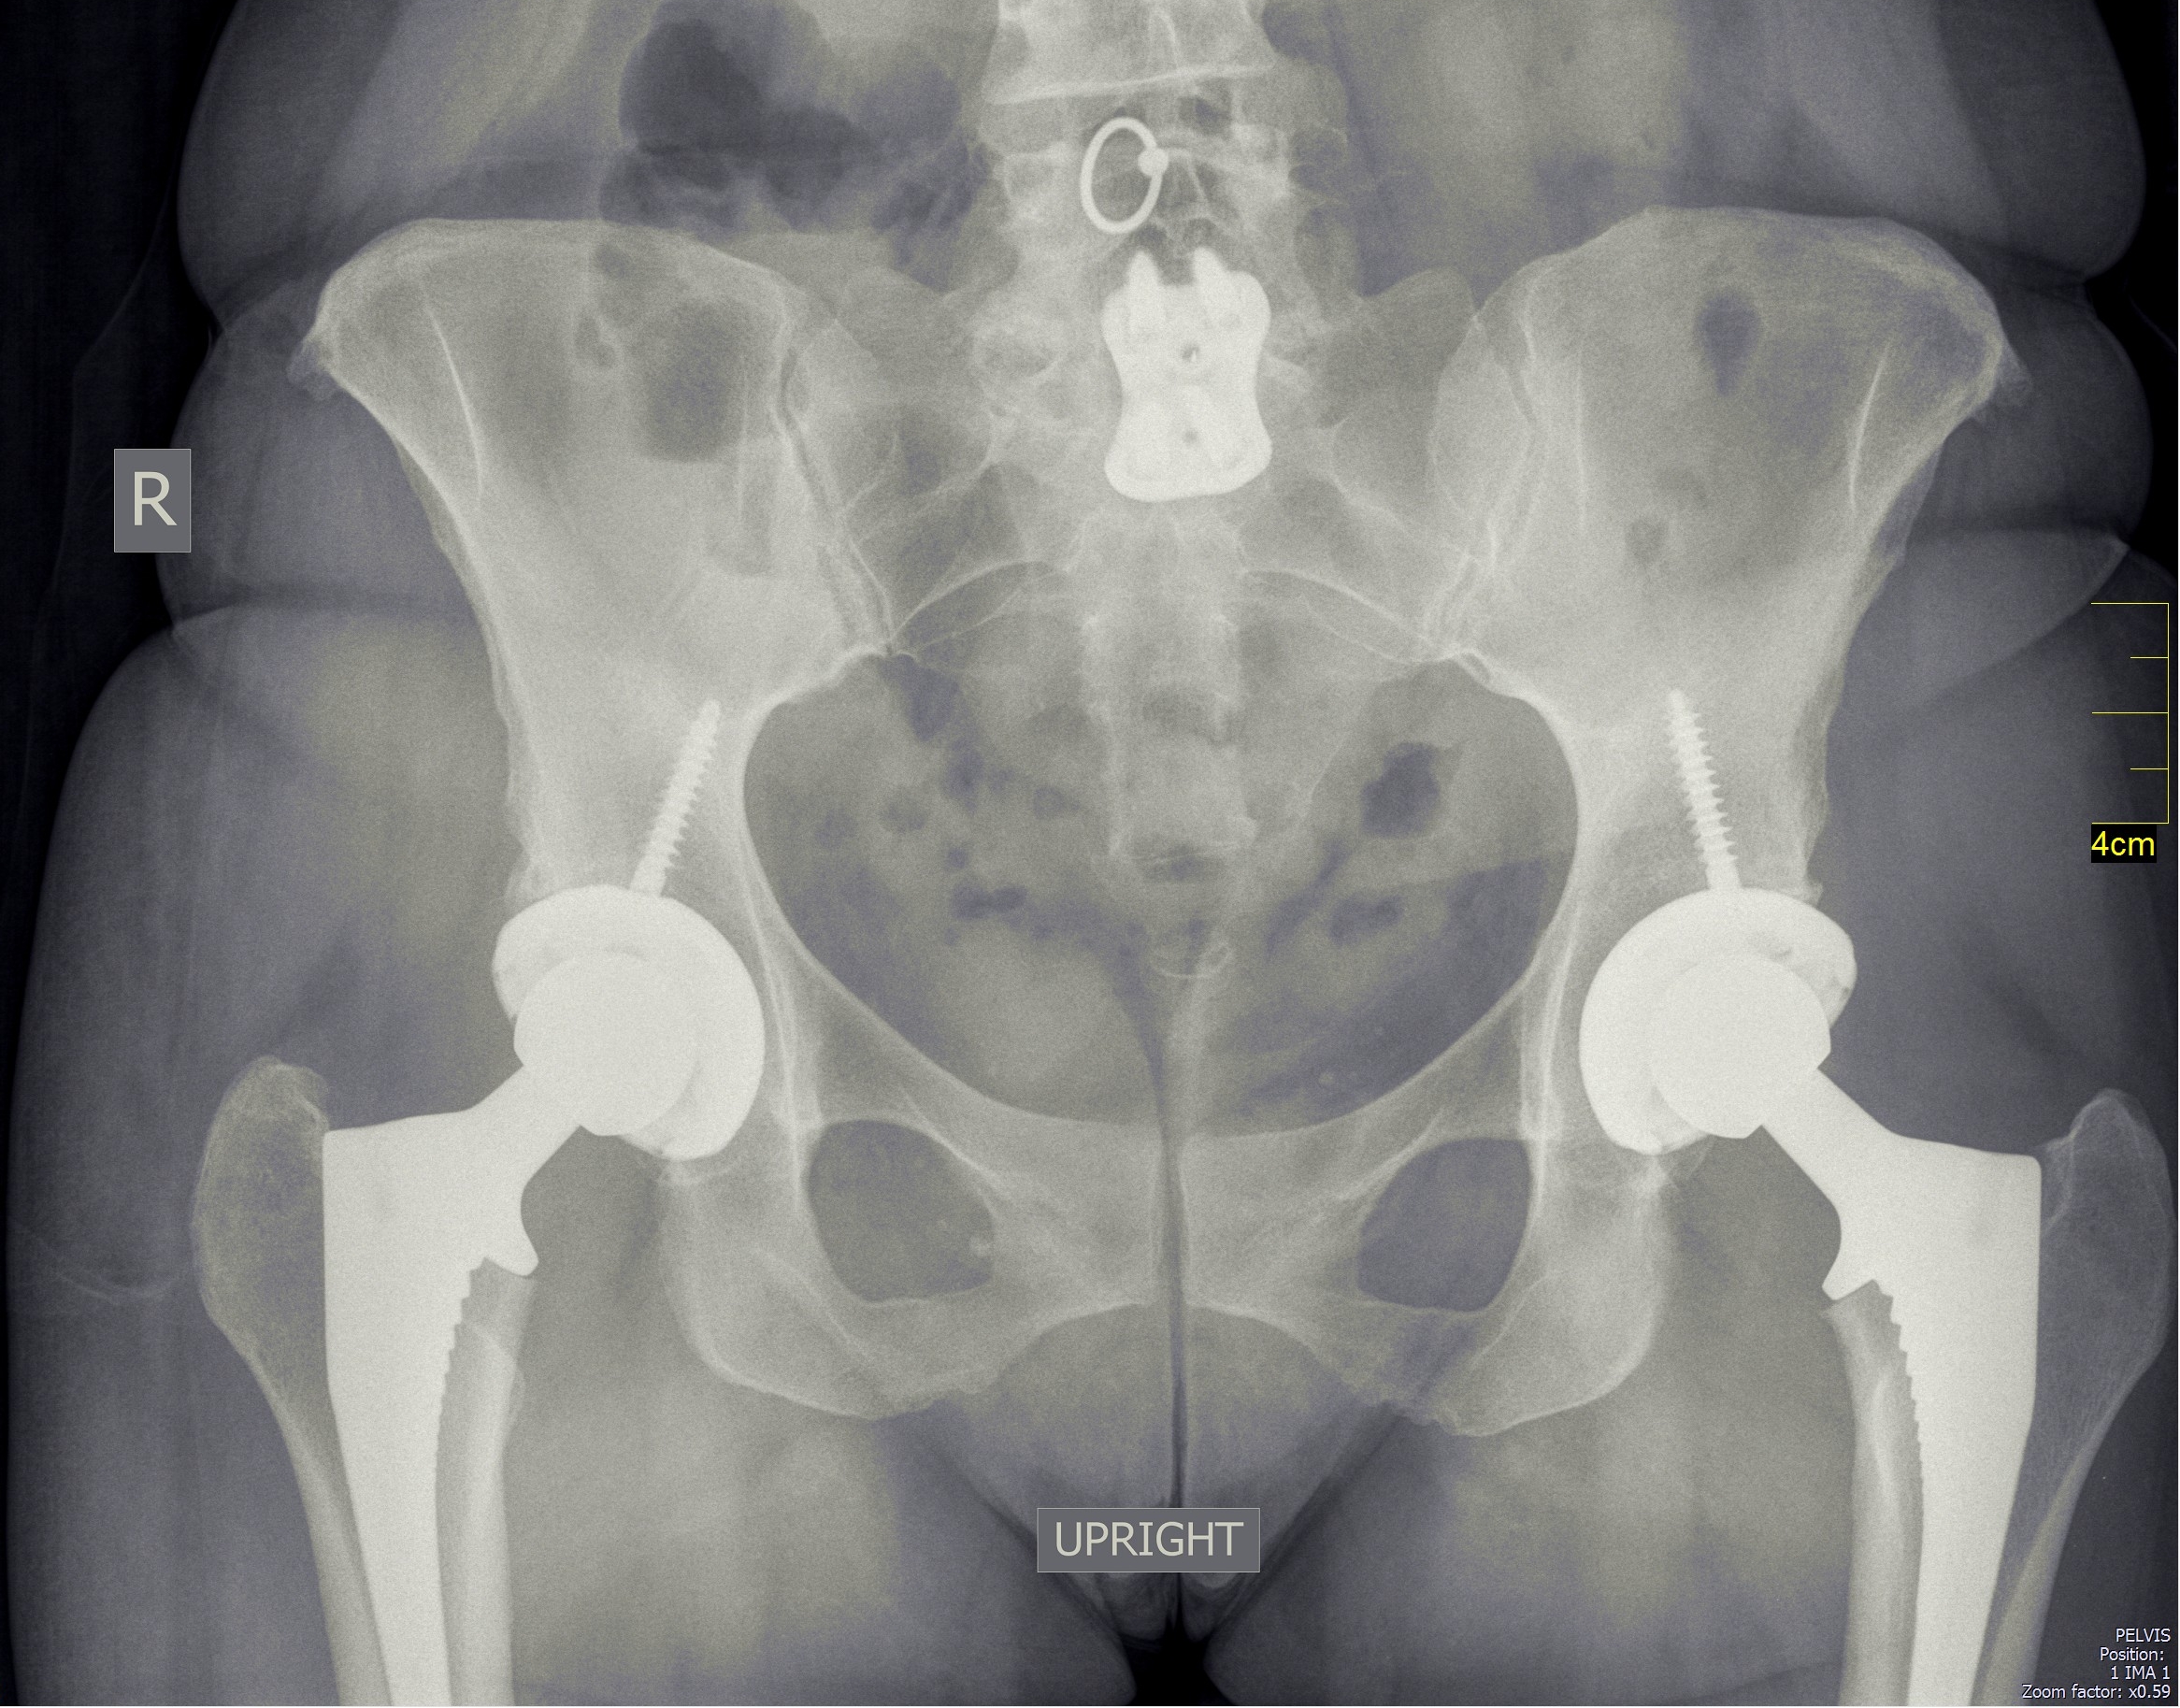

Since the patient is supine, it is possible to perform bilateral simultaneous hip replacements. Here's the appearance of my patient who had both hips replaced: